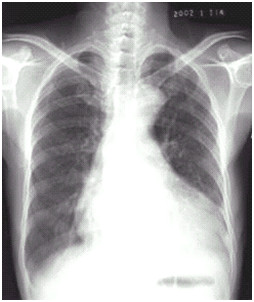

03卷-4.病史:女性,73歲,血壓升高10年,心悸、頭暈、乏力2周。診斷(本題滿分2.00分)

A.梨形心

B.靴形心

C.普大型心臟

D.正常心臟

本題答案:B

題目解析:

【該題針對(duì)“ X線-心臟增大(尖瓣型、主動(dòng)脈型和普大型) ”知識(shí)點(diǎn)進(jìn)行考核】